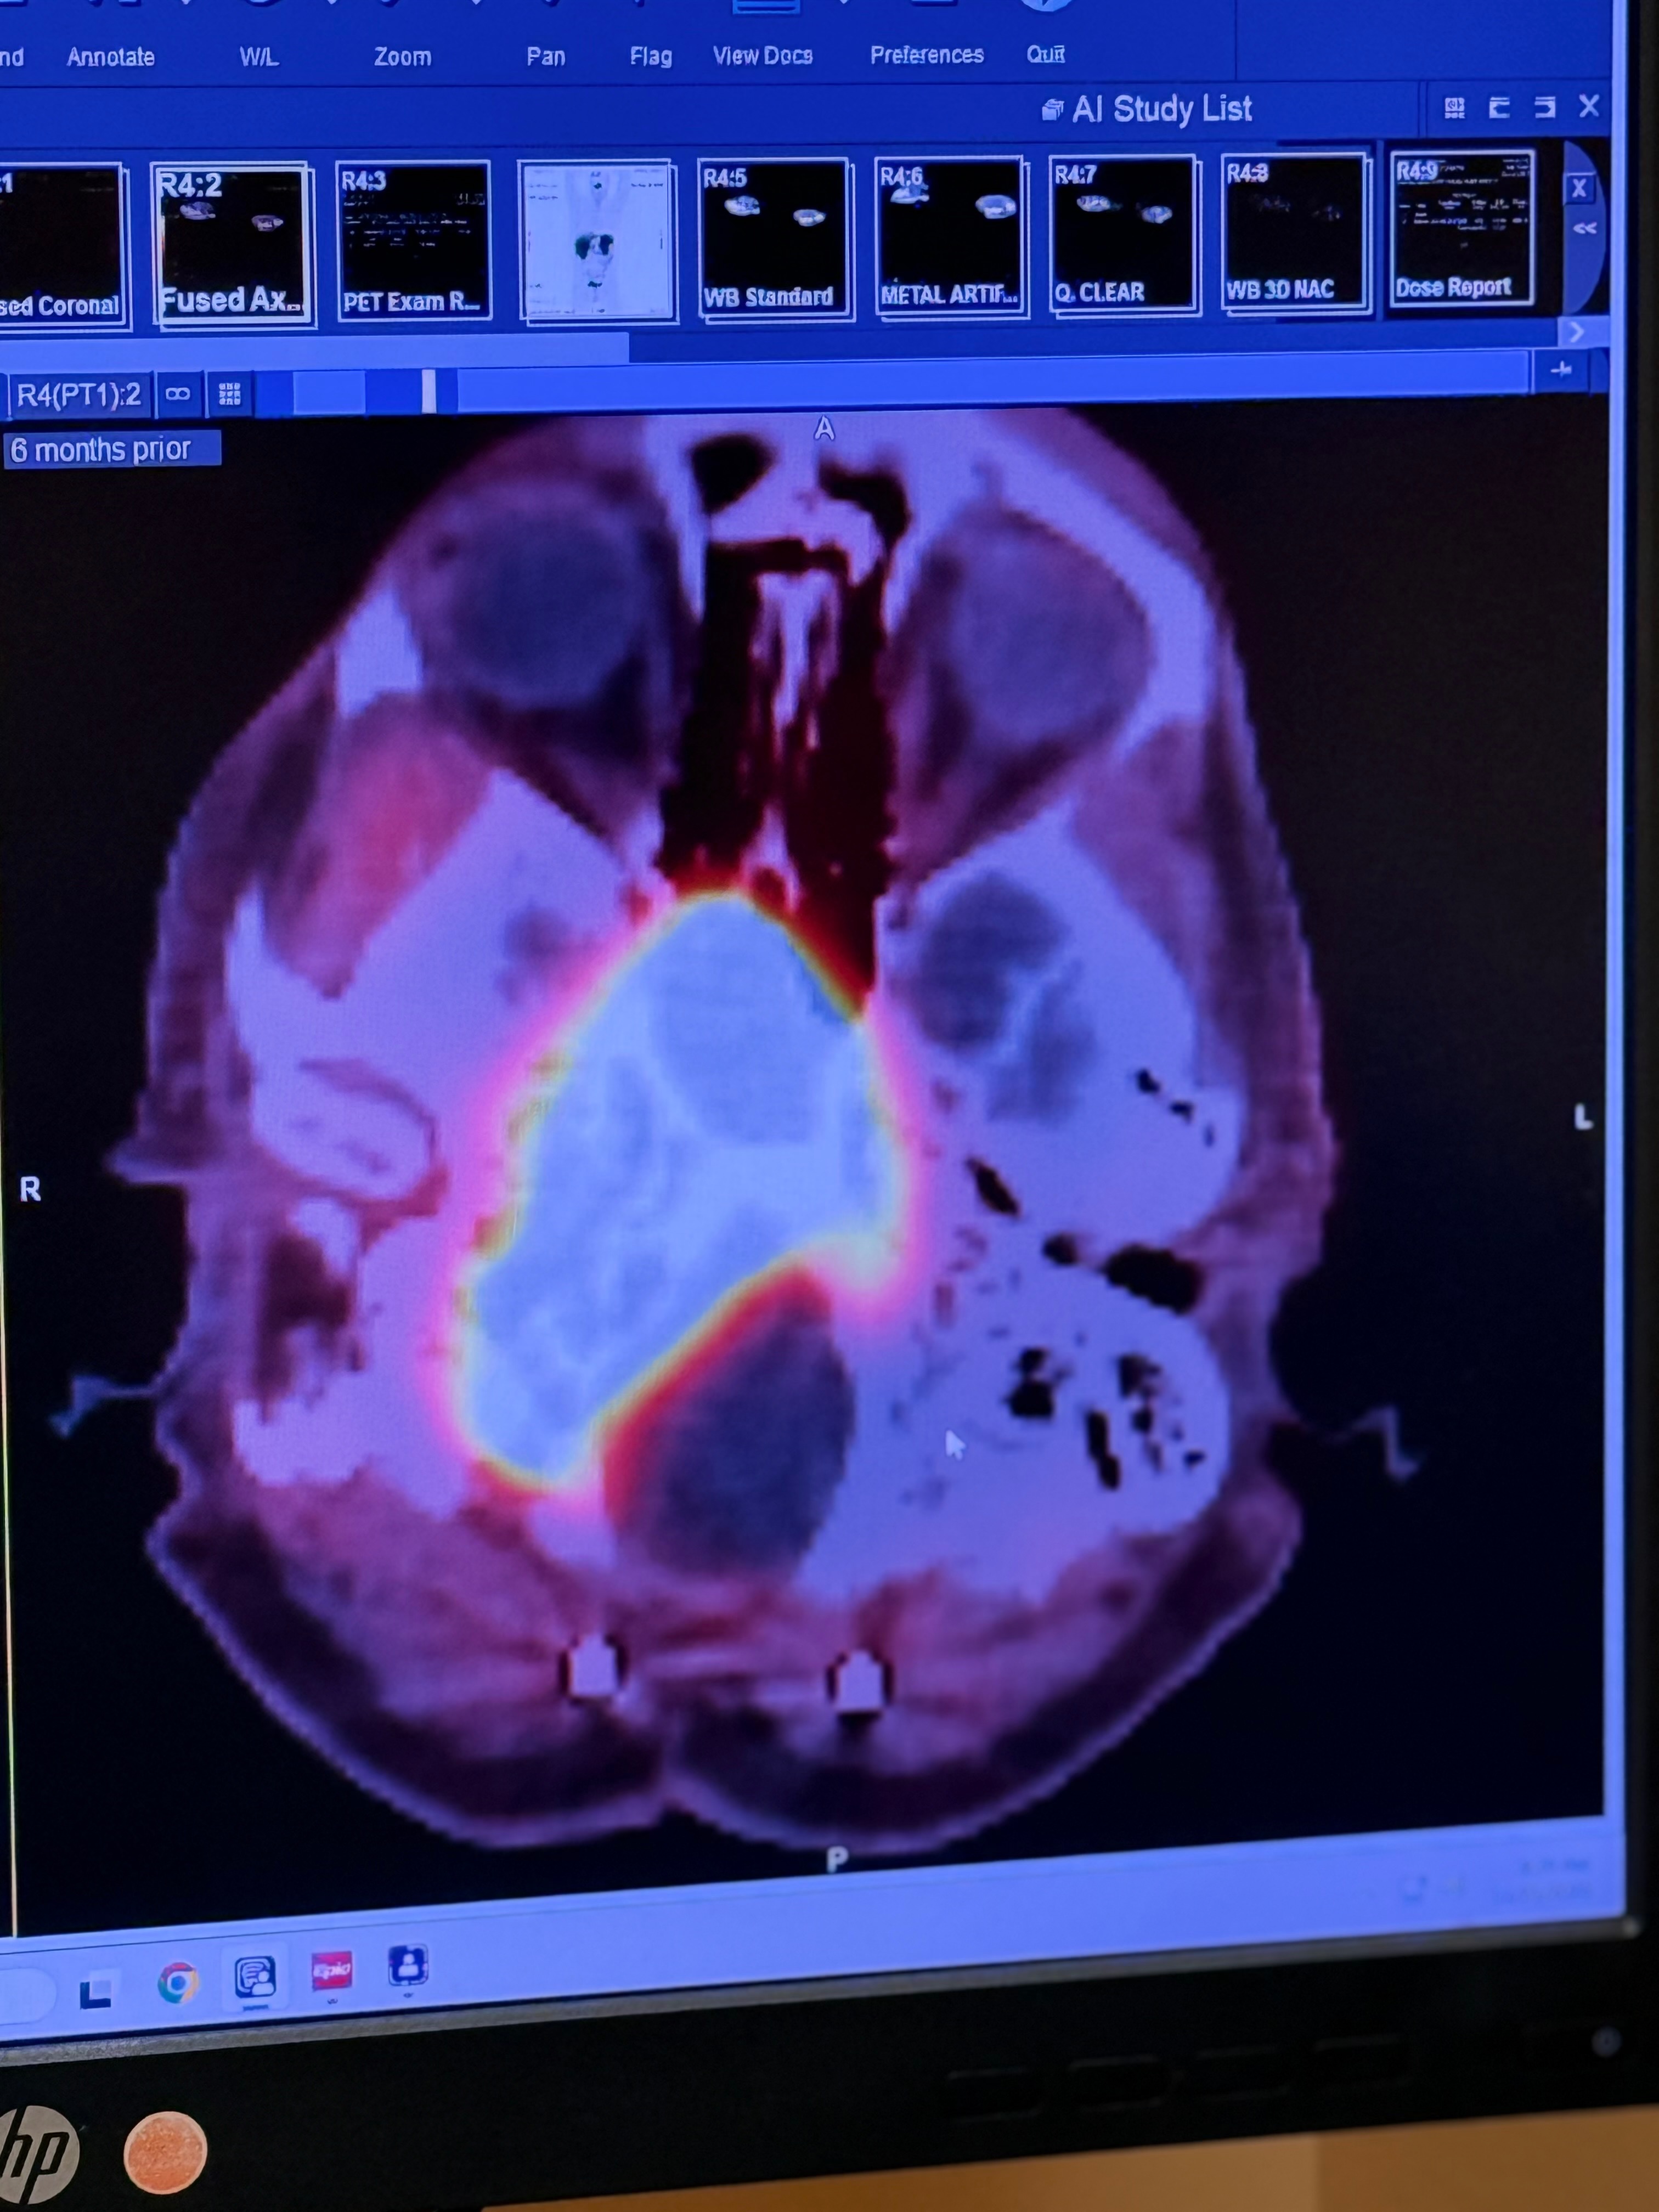

Near the end of 2024, their lives were turned upside down again when Justin was diagnosed with a massive meningioma brain tumor located in an extremely critical area of his brain and spinal column. In December, he underwent a 36-hour brain surgery, but surgeons were only able to remove about one-third of the tumor. Two-thirds of the tumor remains, as removing more would have caused catastrophic damage.

At the beginning of 2024, Justin was diagnosed with kidney cancer, beginning a year that would push their family beyond anything they could have imagined. They navigated treatment and recovery, hoping that chapter would be the hardest one they would face.